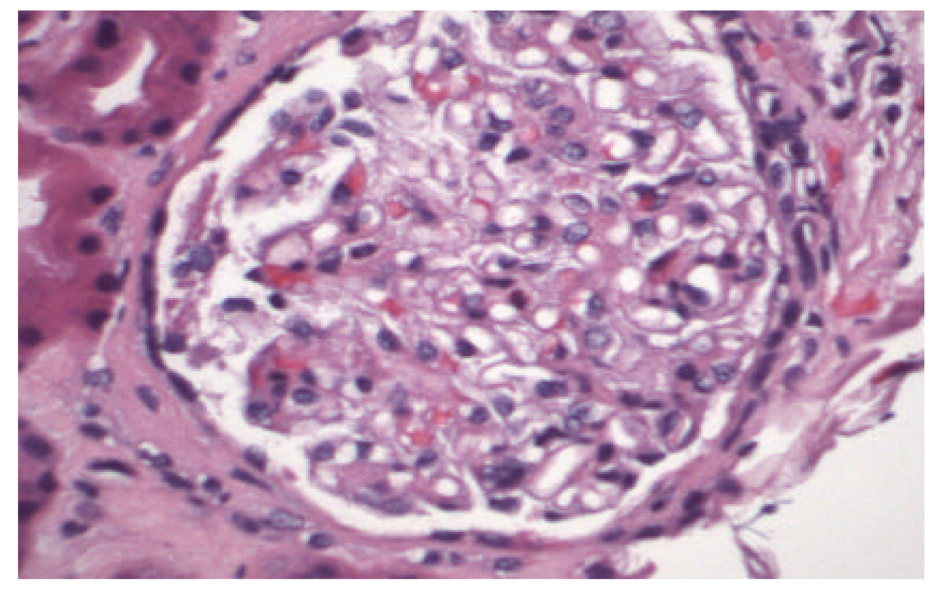

Renal ultrasound showed normal size kidneys with bilateral cortical thinning, and no hydronephrosis. CT scan of the abdomen and pelvis showed a 3.2 cm infrarenal abdominal aortic aneurysm with mural thrombus of undetermined age. Patient was started on dialysis and a percutaneous renal biopsy was performed. The biopsy specimen revealed that 8 out of 26 glomeruli were globally sclerotic and the remaining glomeruli showed diffuse mesangial matrix expansion and focal patchy interstitial fibrosis (Fig. 1). The medium sized arteries were focally occluded by cholesterol clefts surrounded by granulomatous inflammation, and small arterioles with severe arteriolonephrosclerosis, without evidence of vasculitis (Fig. 2, 3). The patient was discharged home with outpatient dialysis arrangements, and he has remained dialysis dependent.

![]() Click for large image | Figure 1. Mild mesangial matrix expansion, otherwise normal glomerulus (Hematoxylin & Eosin, × 4,000). |